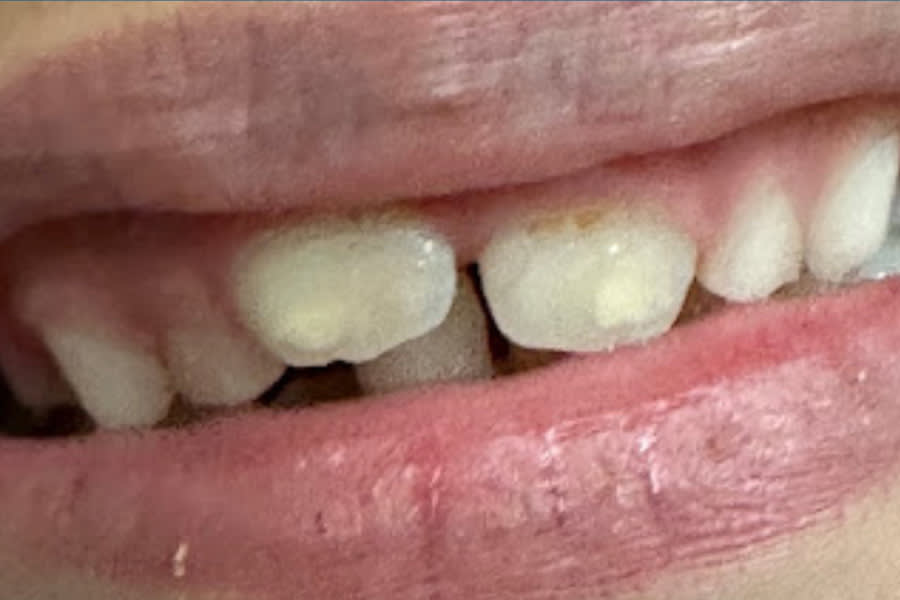

Lucas, an 8-year-old boy (now 10), presented with a history of significant developmental challenges, including ARM/VATER syndrome, multiple early surgeries, and enamel weakness with erosion. Orthodontic appliances, including an expander and, later, a Nance, complicated hygiene. Visual examination revealed white spot lesions on teeth Nos. 8 and 9.

Traditional management might include topical calcium-phosphate-based toothpastes, fluoride varnish, or resin infiltration. However, due to concern for the patient’s age and social development, treatment with Curodont was preferred. Curodont was applied following etching and drying, with Curodont Protect placed for 6 months. Adjuncts included use of a calcium-phosphate-based toothpaste, fluoride rinse, and power brushing.

At 6- and 12-month follow-ups, the lesions demonstrated visible shrinkage, hardened surfaces, and clinical arrest. Lucas tolerated the treatment well, with no anesthesia required. This case illustrates the use of guided hydroxyapatite generation in pediatric patients, providing both clinical efficacy and parental reassurance while preserving esthetic options for the future. (Figure 1 and Figure 2)